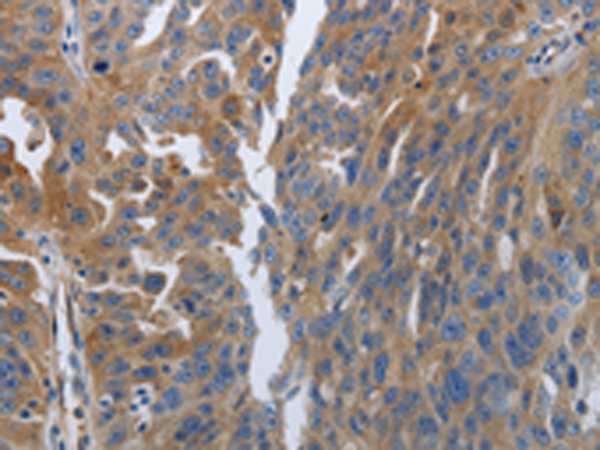

分类: 科研抗体货号: P04203别名: CRCS3; MADH7; MADH8应用: WB,IHC反应种属: Human, Mouse, Rat